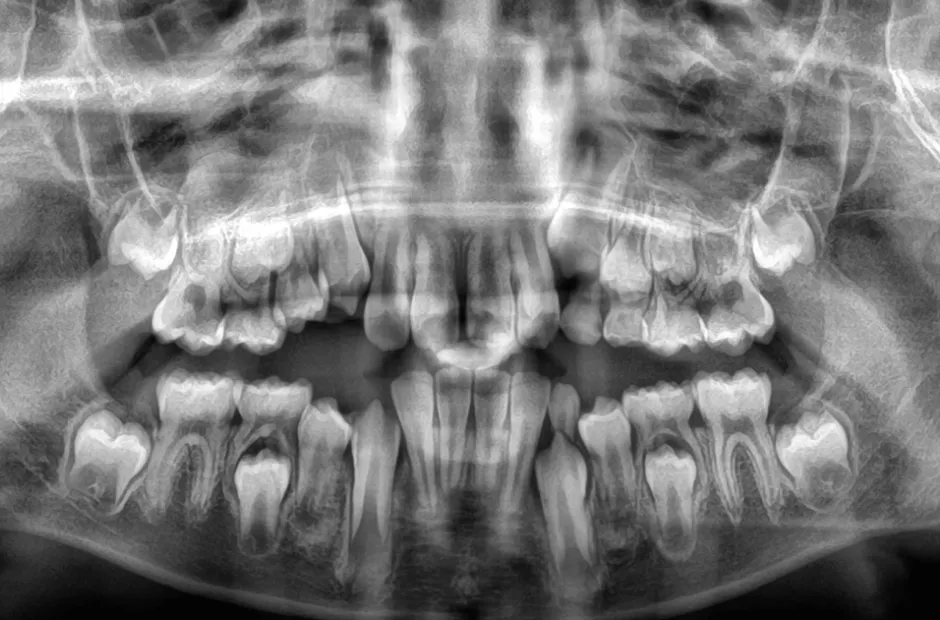

口腔内写真やレントゲンの撮影、歯型取りなど、口や顎の状態を詳しく把握するための精密検査を行ないます。さらに、骨の成長状況や身長・体重の増加傾向、永久歯の生えかわりについても確認します。

「子どもの歯並び、いつから治療を始めるべき?」と悩んでいませんか?小児矯正を始めるベストなタイミングは、永久歯が生え始める6歳頃が目安です。この時期から治療を始めると、将来的にワイヤーを使う本格的な矯正(ブラケット治療)が必要なくなったり、治療期間を大幅に短縮できたりします。これは、子どもの顎の成長を利用して歯が並ぶスペースを確保する「短期集中治療」とも言えるでしょう。また、歯並びが悪いと見た目が気になるだけでなく、うまく噛めないといった機能的な問題も生じます。だからこそ、早い段階で矯正を始めることで、これらの問題を改善し、健康な成長をサポートすることが大切です。さらに、先天的な歯や顎の異常を早期に発見しやすくなるため、もし異常が見つかっても、負担の大きい外科手術などを回避できる可能性が高まります。

先天的な歯や顎の症状

先天的な歯や顎の異常や疾患には、顎変形症や埋伏歯、過剰歯、先天性欠如などがあります。これらの異常や疾患に対し、子どもの時期から適切な処置や矯正治療で歯と顎の発育を正しい方向に導くことができると、将来の大掛かりな治療や外科手術を回避しやすくなります。歯や顎のことで気になることがあれば、お気軽にご相談ください。